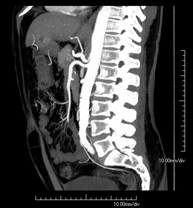

Prova diagnòstica no invasiva que consisteix en l'estudi de l'artèria aorta abdominal a través de l'obtenció d'imatges d'alta definició anatòmica mitjançant l'ús d'un equip de TC (Tomografia Computeritzada) i de contrast iodat. La qualitat de les imatges permet realitzar reconstruccions en 2D i 3D gràcies a estacions de treball especialitzades en l'estudi arterial. Està indicat en aquells pacients amb malaltia vascular (arteriosclerosi), en aneurismes d'aorta, en pacients amb dolor abdominal de possible origen vascular, en estudis prequirúrgics de lesions adjacents a l'aorta abdominal com a "mapa" vascular. La informació obtinguda de manera no invasiva és indispensable per als pacients que requereixen tractament percutani o quirúrgic. En aquells pacients que només requereixen seguiment de les lesions vasculars, aquesta tècnica és la tècnica no invasiva d'elecció juntament amb l'angio-RM. - Angio-TC Artèries renals

A non-invasive diagnostic test that involves studying the abdominal aorta by obtaining high-definition anatomical images using CT (computed tomography) equipment and iodinated contrast. With the aid of workstations specialised for arterial studies, the image quality supports 2D and 3D reconstructions. It is indicated in patients with vascular disease (atherosclerosis), aortic aneurysms, abdominal pain of possible vascular origin, pre-surgical studies of lesions adjacent to the abdominal aorta as a vascular ‘map’, etc. Information obtained non-invasively is indispensable for patients requiring percutaneous or surgical processing. In patients who only require tracking of vascular lesions, this technique is the non-invasive technique of choice, together with MRI angiography.